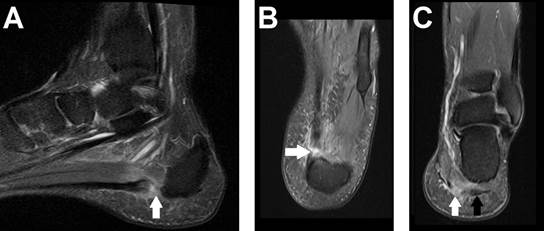

A 42-year-old man developed severe left foot pain after hearing a “pop” while playing soccer. He had experienced plantar pain for three months, aggravated by wearing boots at work. Examination revealed plantar tenderness without significant bruising or swelling, and he walked with a limp. MRI showed plantar fasciitis in the lateral band and a complete rupture of the central band at its insertion (Figure 1). He was treated with analgesics and physical therapy, achieving full recovery in three months.

Figure 1: DP FAT SAT MRI in sagittal (A), axial (B), and coronal (C) sections showing a complete rupture of the central band of the plantar fascia (white arrows) and plantar fasciitis in the lateral band of the plantar fascia (black arrow).